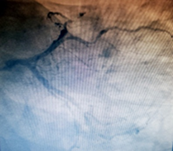

Figure 1 Circumflex artery and second left marginal branch, of great importance, diffusely atheromatous, with segmental lesion of 80% in the middle third.

Figure 2 Anterior Descending Artery exceeds the tip of the heart, is occluded in the middle third and first diagonal branch, of great importance, presents with a 70% lesion in the ostium, followed by a segmental lesion of 70% in the middle third.

Figure 3 Dominant right coronary artery, irrigates part of the posterior wall of the left ventricle, is occluded in the middle third and posterior descending artery, of little importance, presents with a lesion of 70% in the middle third.